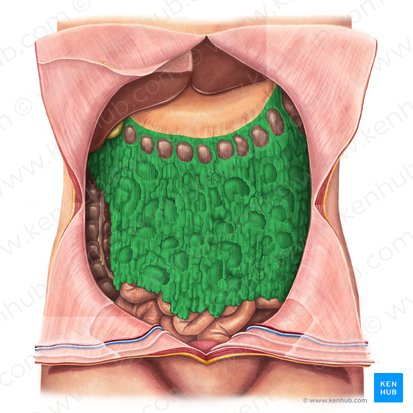

Jejunum

Ileum

Epiploic appendages

Haustra

Taenia coli

Ileocecal valve

Cecum

Appendix

Ascending colon

Right colic flexure

Transverse colon

Left colic flexure

Descending colon

Sigmoid colon